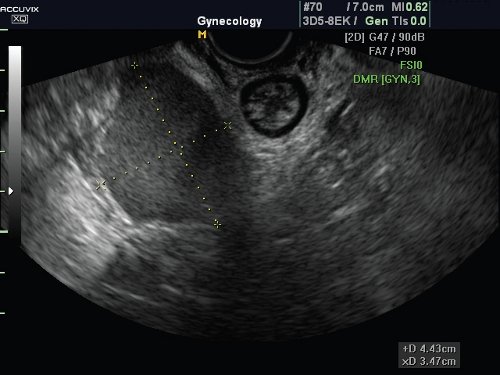

Характерной эхографической особенностью после апоневротической фиксации матки или купола влагалища является высокое стояние купола влагалища, гиперкоррекция заднего уретровезикального угла за счет натяжения передней стенки влагалища. Признаки цистоцеле в форме остроугольного треугольника зафиксированы в 12,5% случаев, что, по нашим данным, является симптомом дефекта лобково-шеечной фасции (рис. 1).

Рис. 1. Гиперкоррекция заднего мочепузырного угла после апоневротической вагинопексии.